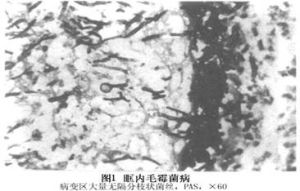

真菌可侵犯血管,引起血栓形成,這樣加重炎症和組織壞死,同時有大量多形核白細胞浸潤,壞死組織周圍可見肉芽腫性反應手術切除的病變組織,用蘇木精嗜伊紅染色能顯示出菌絲,該菌絲對蘇木素有親和力,PAS染色顯示更清楚菌絲寬30~50μm無隔呈分支狀。